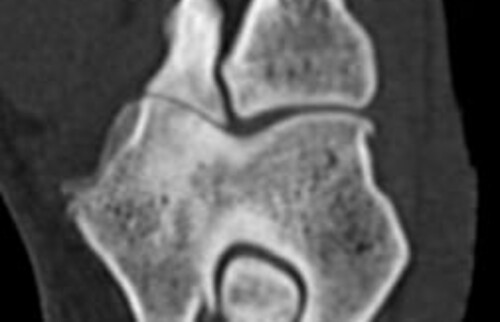

Nach der klinischen Diagnose werden die Hunde in unserer Klinik direkt im Computertomografen untersucht, sodass genau beurteilt werden kann, welche Gelenksanteile wie schwer betroffen sind, um eine individuelle Therapie festzulegen.

Schwarz-weiss Röntgenaufnahme